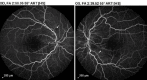

Bilateral Lupus Chorioretinopathy in a Patient With Active Systemic Lupus Erythematosus

Ocular involvement is commonly seen in systemic lupus erythematosus (SLE). However, chorioretinopathy is an easily missed ocular manifestation of SLE. Early recognition and a multidisciplinary treatment approach can play a key role in reducing the ocular and systemic morbidity seen with this condition. This case report describes a patient with active SLE who presented with bilateral lupus chorioretinopathy. The patient demonstrated a significant improvement in ocular symptoms once the systemic disease was controlled.